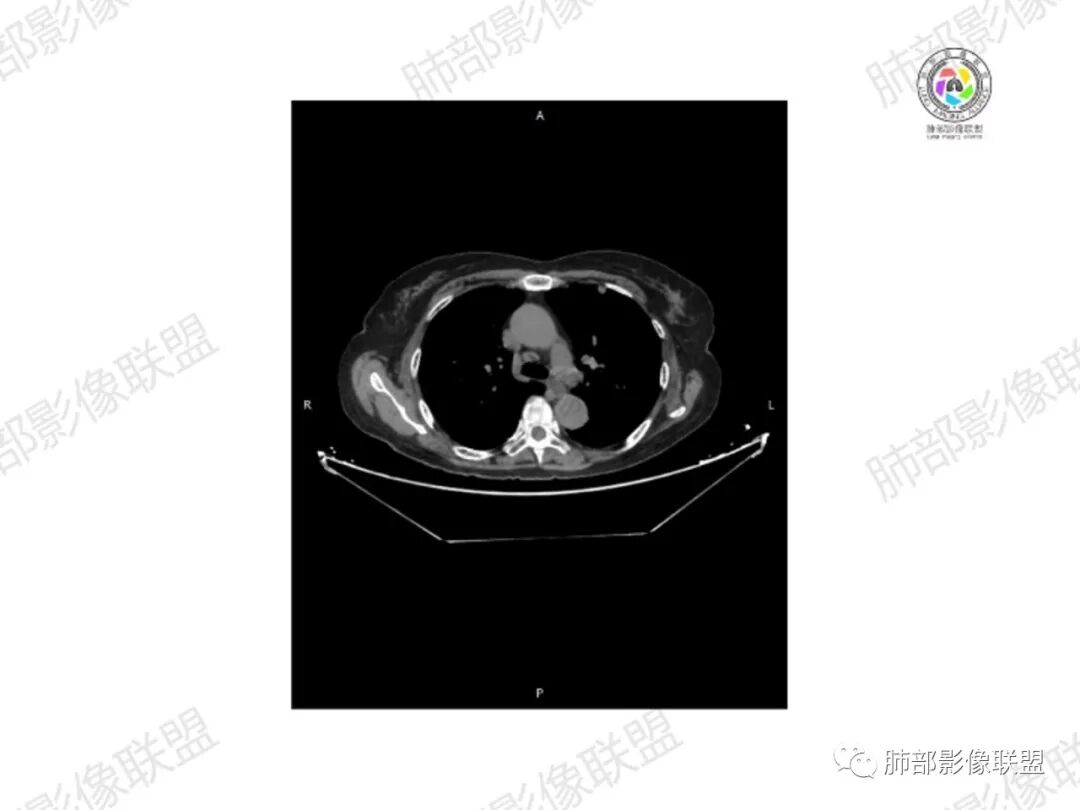

5.双肺多发类圆形结节影,边界清楚,随机分布,其间多见钙化密度影。

6.双肺门及纵隔未见肿大淋巴结。

7.扫描范围内双侧乳腺未见明显块影。

3.双肺病灶符合转移瘤,伴有中央部分钙化者也以骨肉瘤转移较为多见。